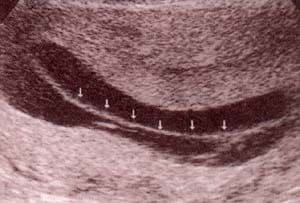

| fig. 53.– (c). polos cefálicos . | fig. 53.– (d). corte transversal a nivel del abdomen en embarazo bicorial – biamniótico. |